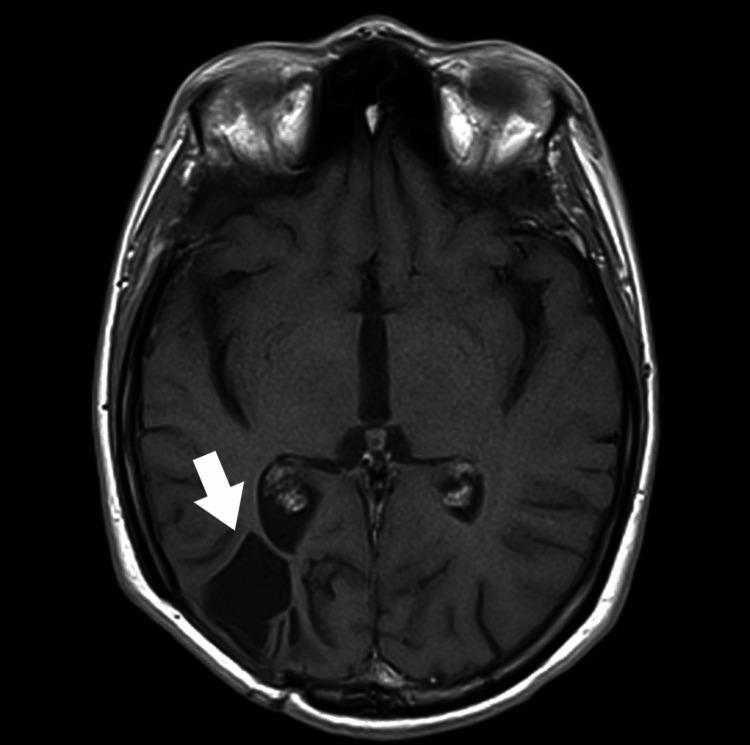

A brain abscess (BA) is a purulent infection of the central nervous system and can be associated with dental procedures. The paper presents a case of a patient diagnosed with an odontogenic BA. On admission, the patient was awake, alert, and oriented (Glasgow Coma Scale 15). The patient reported undergoing excision and drainage of an abscess in the submandibular area three years earlier. An MRI of the head showed a mass lesion (34x19x25 mm) located in the right parieto-occipital region, and an abscess was suspected. During the procedure, puncture and evacuation of the contents of the abscess in the right parieto-occipital area were performed. Oral microorganisms, including and , were isolated from the brain pus. A thorough radiographic and dental examination should be conducted during hospitalization in these patients. Always evaluate for periapical pathology in unexplained BAs, even in the absence of oral symptoms.

脑脓肿(BA)是中枢神经系统的化脓性感染,可能与牙科手术有关。本文介绍了一例被诊断为牙源性脑脓肿的患者。入院时,患者清醒、警觉且定向力正常(格拉斯哥昏迷量表评分为15分)。患者报告三年前曾接受下颌下区脓肿的切除和引流手术。头部MRI显示右顶枕区有一个肿块病变(34×19×25mm),怀疑为脓肿。手术过程中,对右顶枕区脓肿内容物进行了穿刺和引流。从脑脓液中分离出包括[具体微生物名称1]和[具体微生物名称2]在内的口腔微生物。对这些患者住院期间应进行全面的影像学和牙科检查。即使没有口腔症状,对于不明原因的脑脓肿也应始终评估根尖周病变情况。